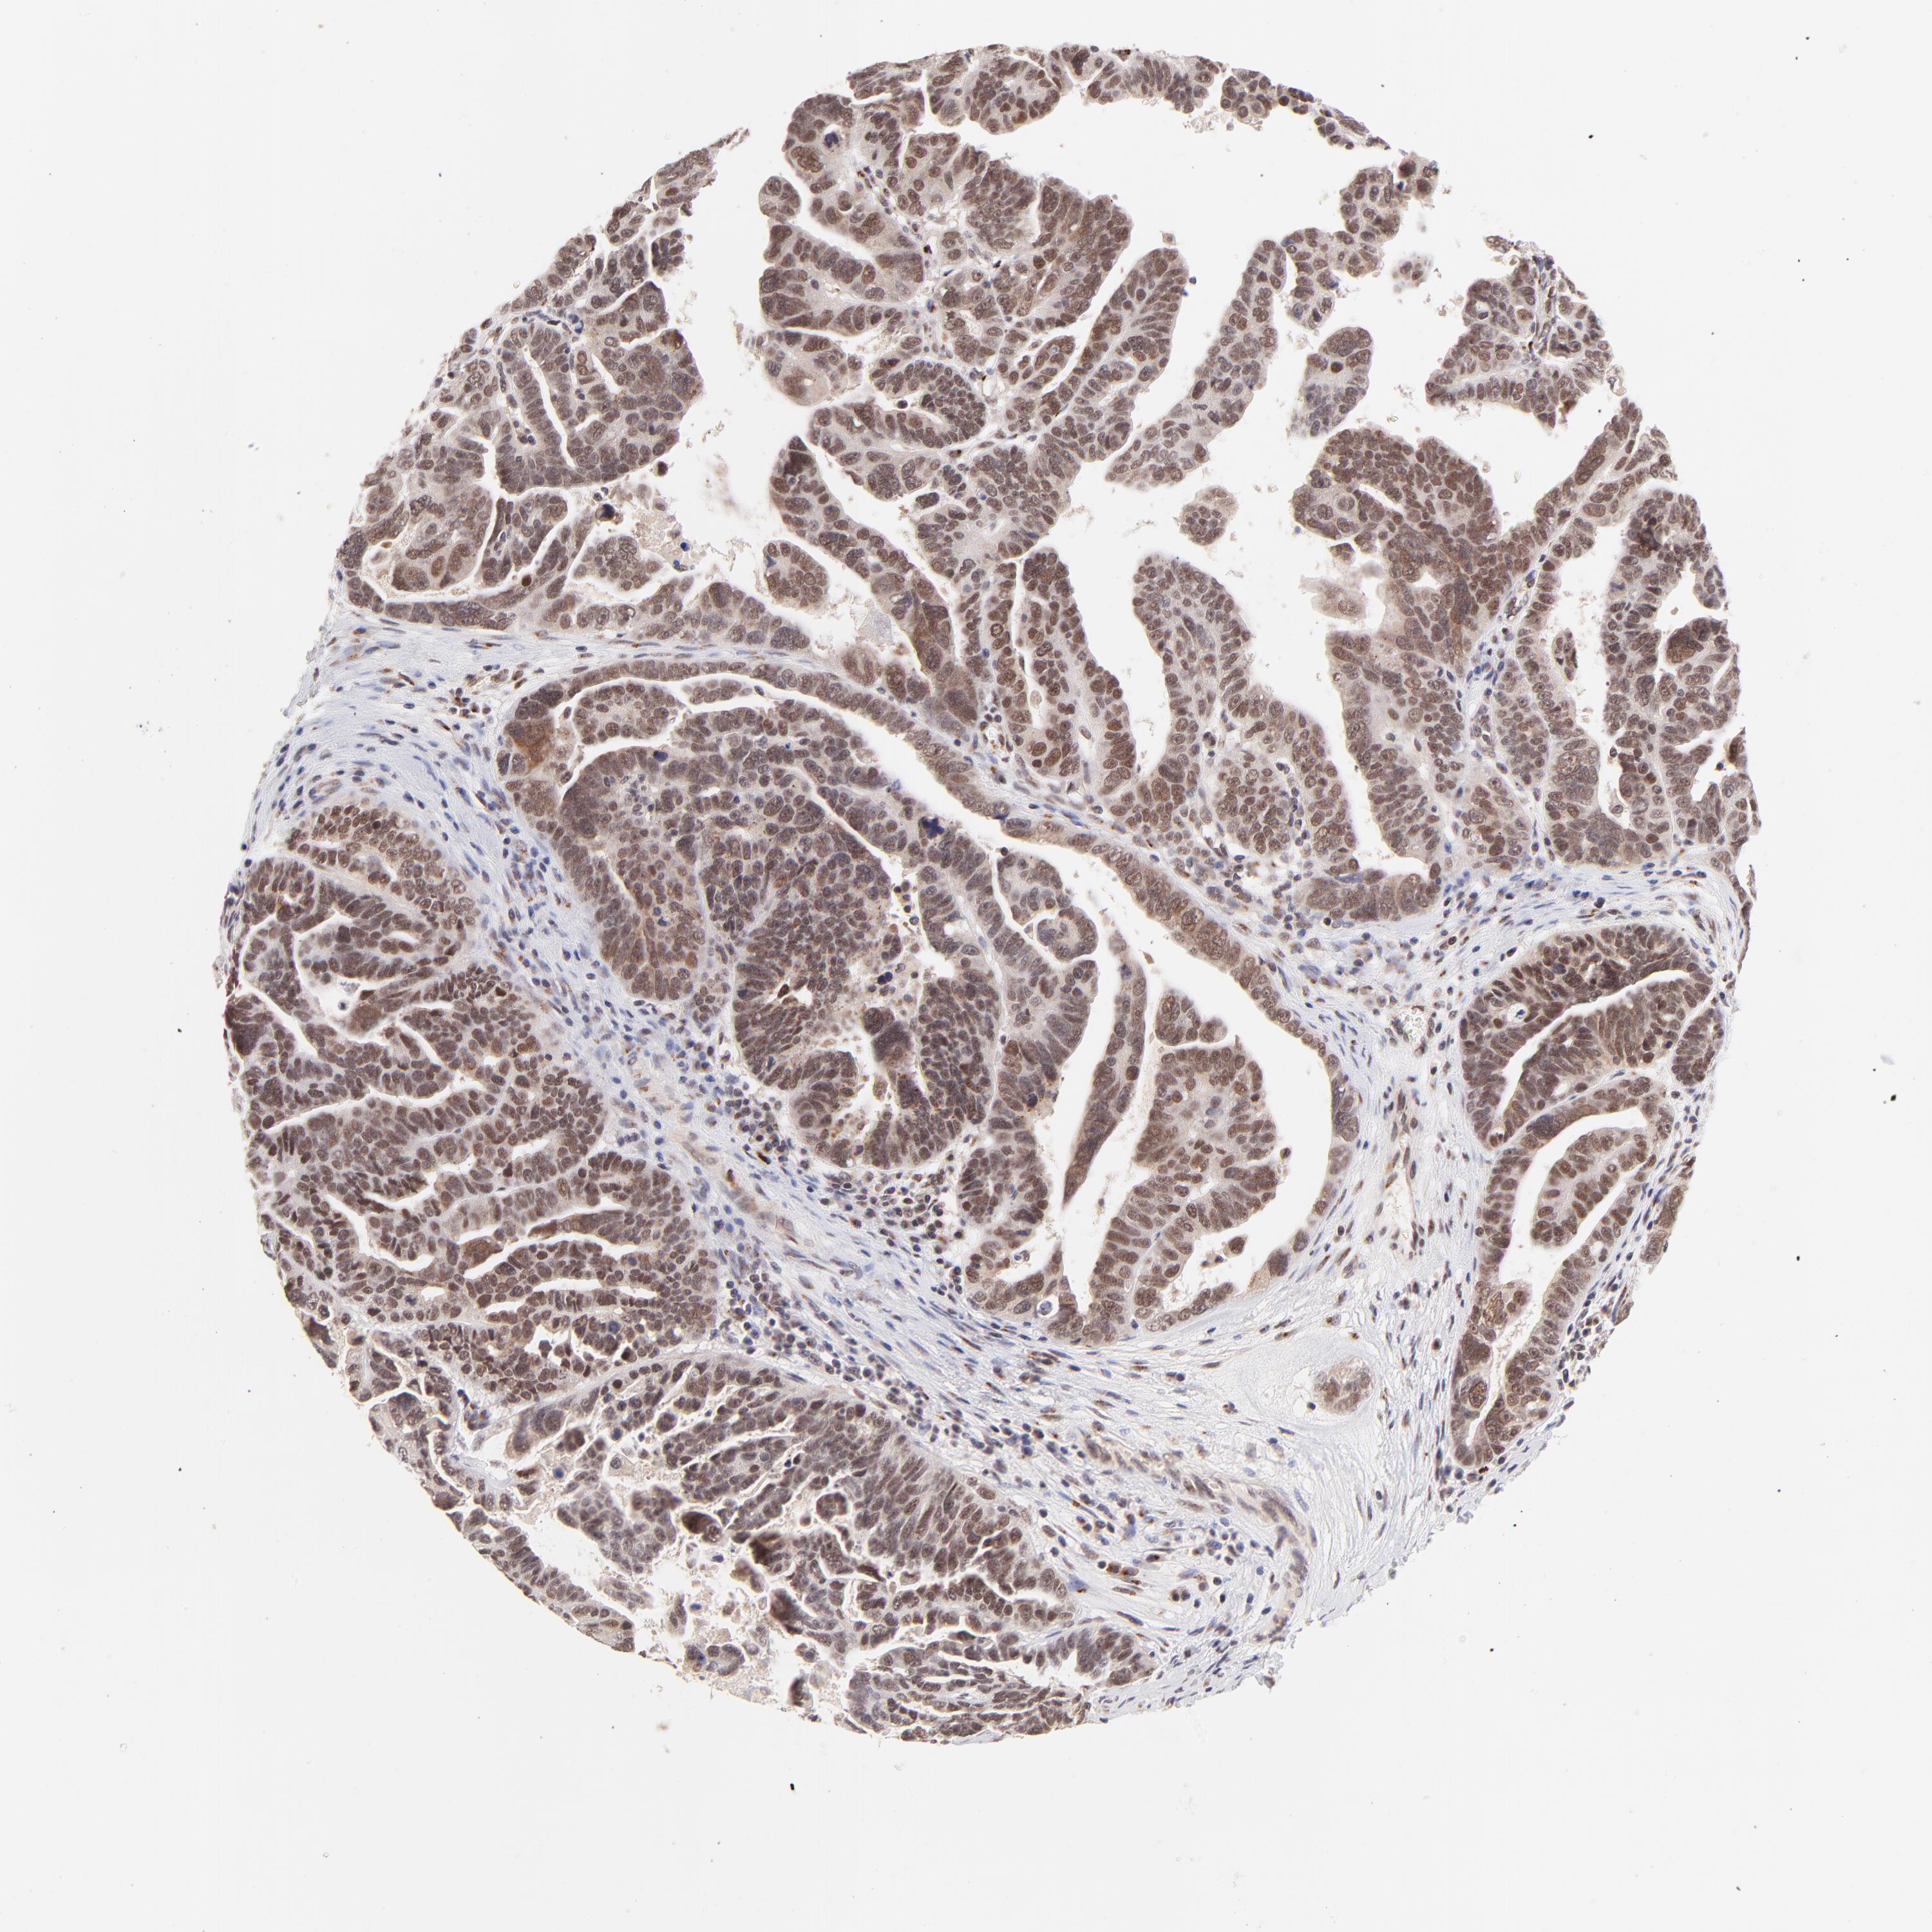

OVARIAN CANCER - Protein expressioni

A mouse-over function shows sample information and annotation data. Click on an image to view it in a full screen mode. Samples can be filtered based on level of antibody staining by selecting one or several of the following categories: high, medium, low and not detected. The assay and annotation is described here.

Note that samples used for immunohistochemistry by the Human Protein Atlas do not correspond to samples in the TCGA dataset.

Antibody stainingi

Antibody staining in the annotated cell types in the current human tissue is reported as not detected, low, medium, or high, based on conventional immunohistochemistry profiling in selected tissues. This score is based on the combination of the staining intensity and fraction of stained cells.

Each image is clickable and will lead to virtual microscopy that enables deeper exploration of all samples and also displays staining intensity scores, fraction scores and subcellular localization as well as patient and tissue information for each sample.

Antibody HPA003184

Antibody HPA003185

Cystadenocarcinoma, mucinous, NOS

Carcinoma, endometroid

Cystadenocarcinoma, serous, NOS